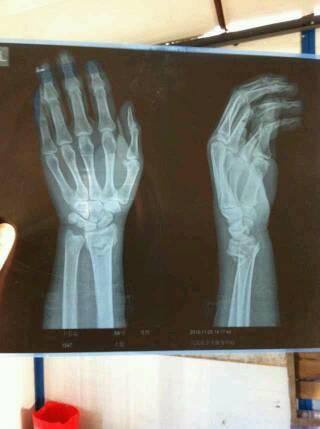

左手桡骨远端骨折图

左手桡骨远端骨折图,正常左手桡骨远端图片

我的左手桡骨远端骨折.在医院医生接上过后就上了4块夹板.

患者59岁,左桡骨远端骨折,骨折断端明显

前些天骑车不小心摔的 左手桡骨远端骨折 我想问,除了这个,还有其他

左手桡骨远端骨折图片

左侧桡骨远端骨折图片

桡骨远端骨折图片

左尺桡骨远端骨折图片